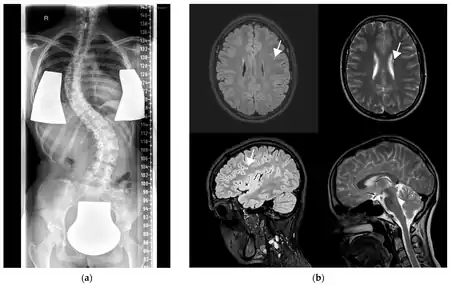

a) X-ray showing scoliosis b) MRI with left frontal FLAIR hyperintensity